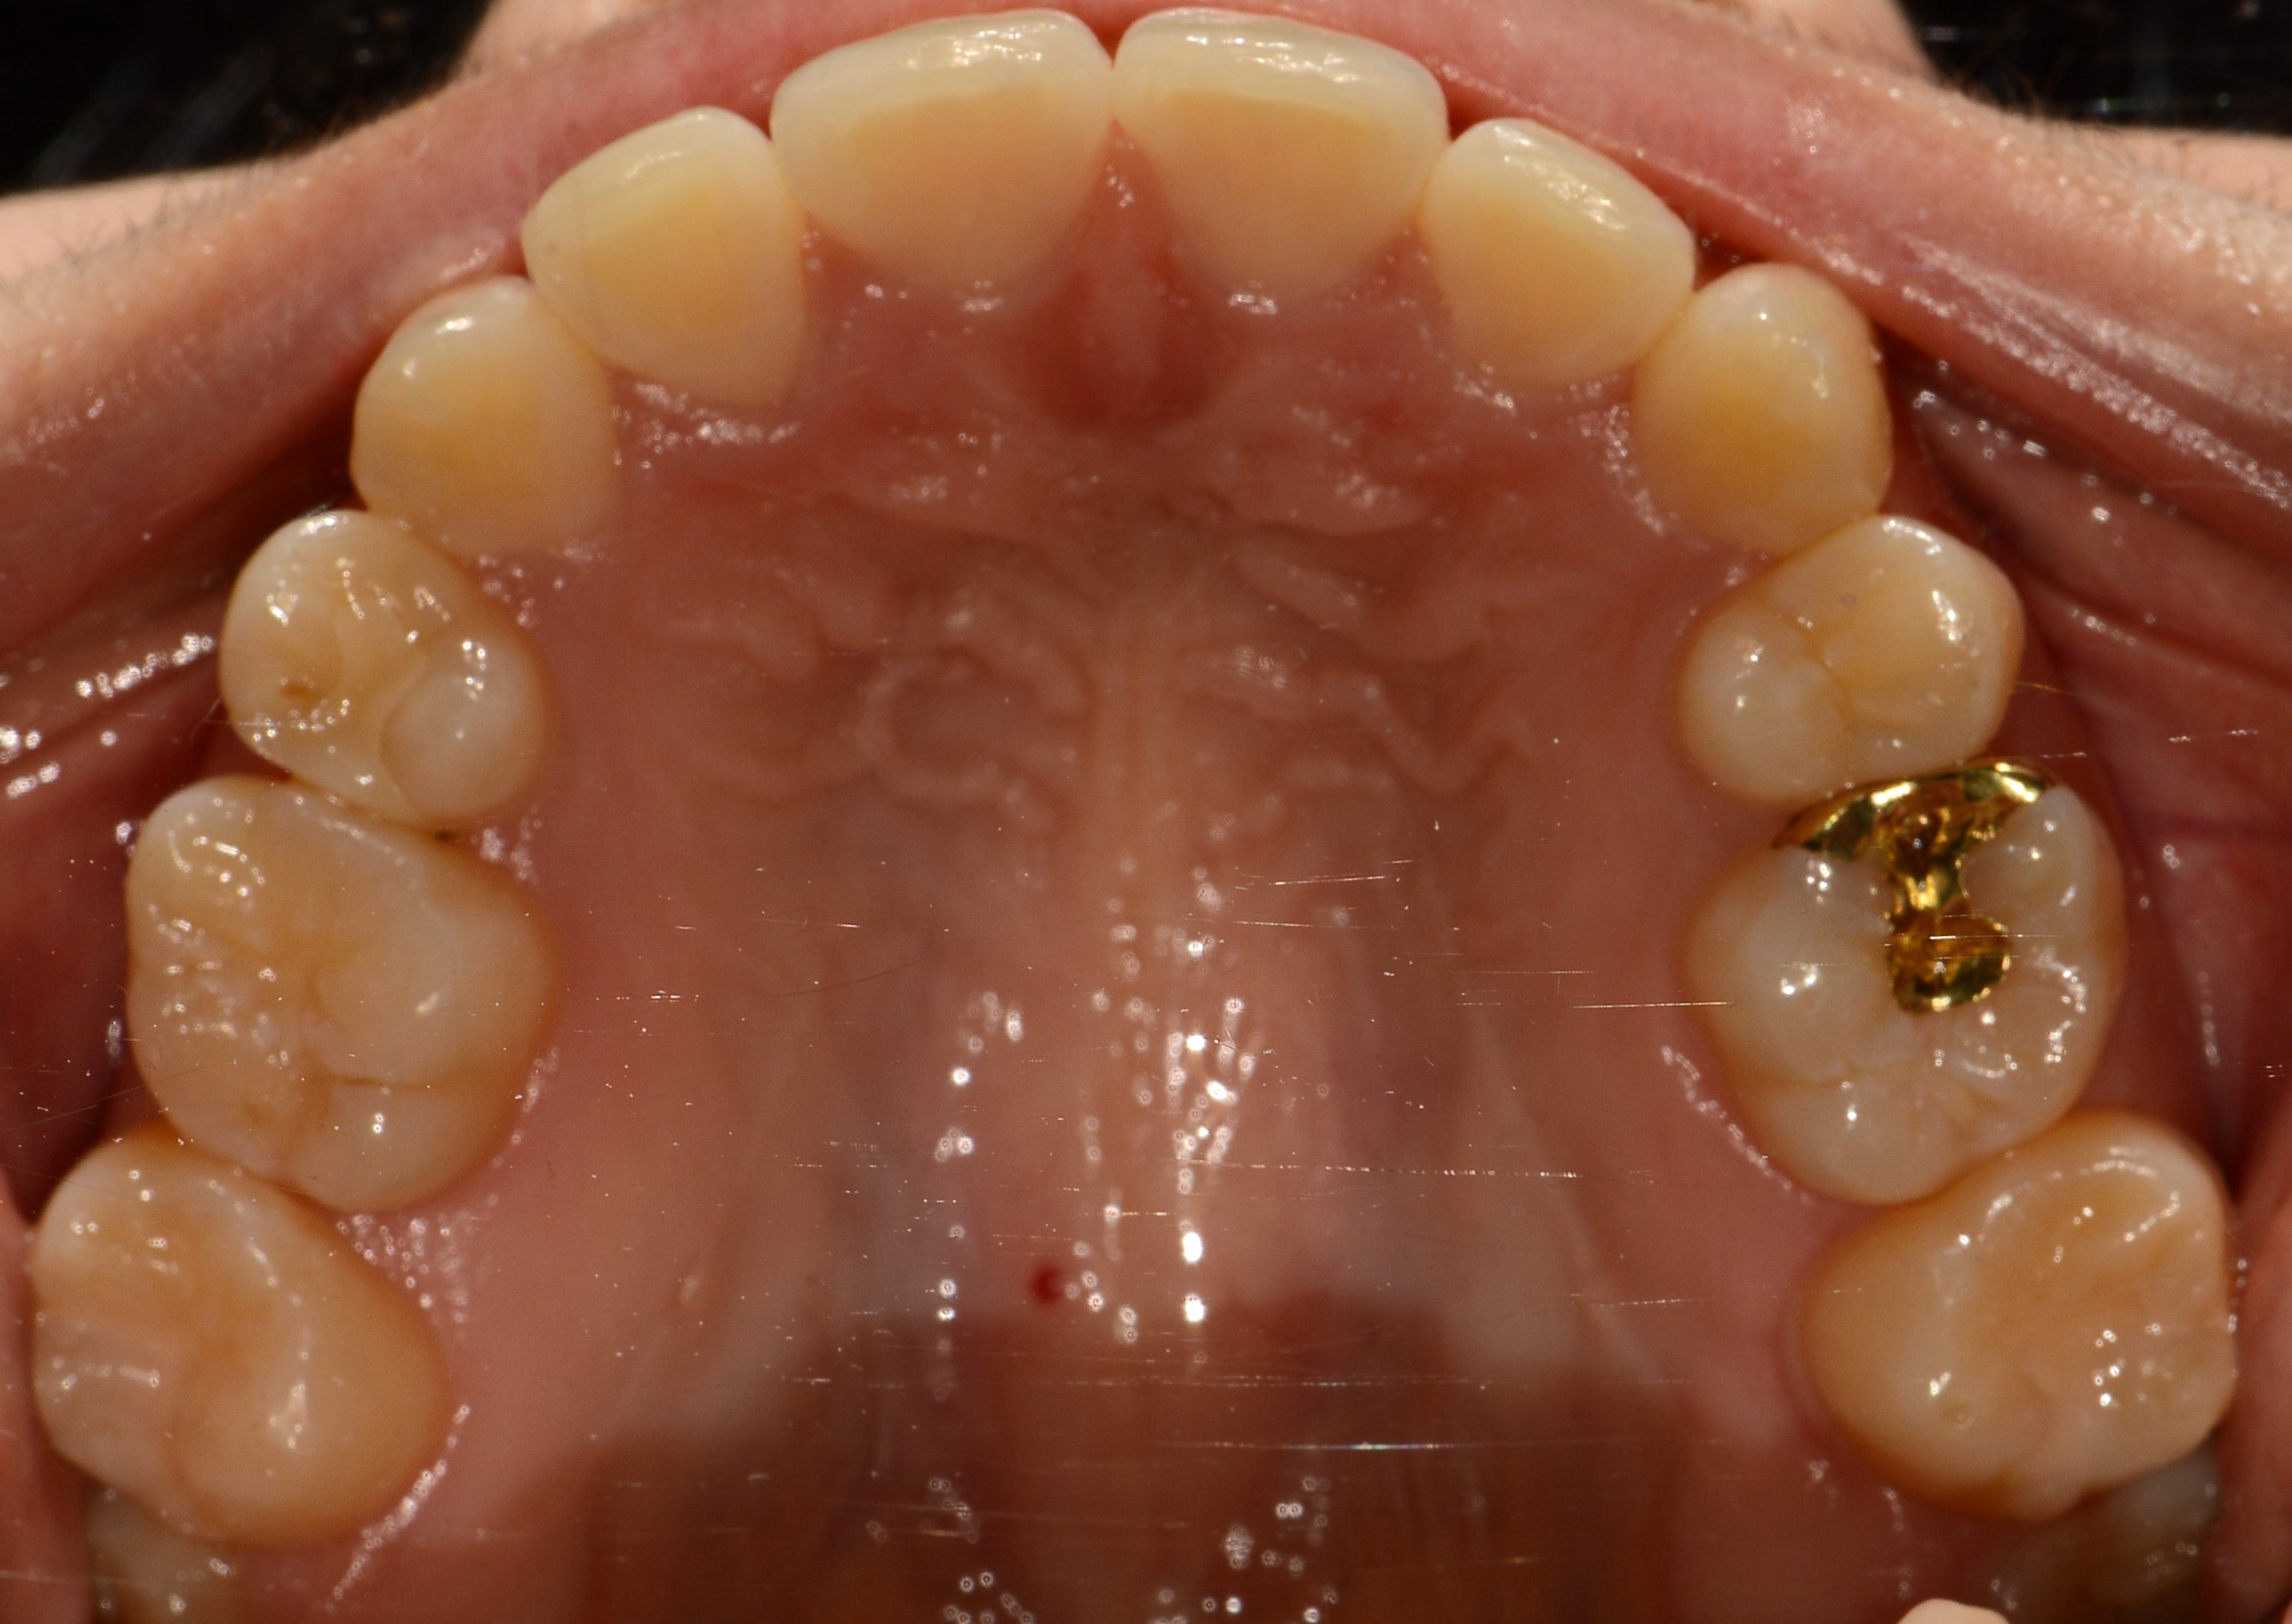

치료 후 사진입니다.